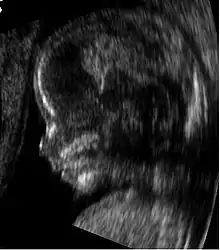

![]() Obstetric sonogram of a fetus at 16 weeks. The bright white circle center-right is the head, which faces to the left. Features include the forehead at 10 o'clock, the left ear toward the center at 7 o'clock and the right hand covering the eyes at 9:00. | |